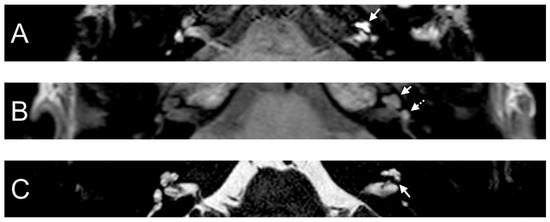

A 38-year-old female presented with a sudden hearing loss on the left side with acute rotatory vertigo without tinnitus. The visual examination showed a spontaneous nystagmus to the right side. The audiogram revealed a PTA of 110 dB on the left. Intraoperatively, a PLF track around the RW niche was observed, but the CTP on the left side was negative. Hyperintense signal intensity was found on T1- and CE-T1-weighted MRI sequences. On the T2 sequence, a hypointense signal in cochlear basal turn was found on the affected side in comparison to the contralateral side. In consideration of T1 and T2 sequences and acute symptom development, we assumed that labyrinthitis caused the sudden hearing loss in this case. On the 4 h delayed 3D-FLAIR image, a contrast enhancement was found in the cochlea, vestibulum, and fundus on the side of hearing loss (Figure 2).

Figure 2. A 38-year-old female presented with sudden hearing loss on the left side and acute rotatory vertigo. The axial 4 h delayed 3D FLAIR sequence shows a contrast enhancement in the left cochlea (A). A cochlear (arrow) and vestibular (dashed arrow) contrast enhancement was observed in the axial T1 sequence (B). Hypointense signal intensity in the basal turn of the left cochlea was found on axial T2W (C).